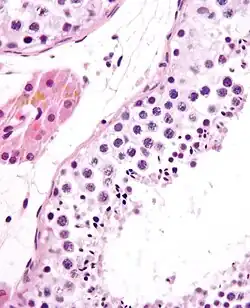

Seminiferous tubule with maturing sperm. H&E stain. | |

Spermatogenesis is the process by which haploid spermatozoa develop from germ cells in the seminiferous tubules of the testicle. This process starts with the mitotic division of the stem cells located close to the basement membrane of the tubules.[1] These cells are called spermatogonial stem cells. The mitotic division of these produces two types of cells. Type A cells replenish the stem cells, and type B cells differentiate into primary spermatocytes. The primary spermatocyte divides meiotically (Meiosis I) into two secondary spermatocytes; each secondary spermatocyte divides into two equal haploid spermatids by Meiosis II. The spermatids are transformed into spermatozoa (sperm) by the process of spermiogenesis. These develop into mature spermatozoa, also known as sperm cells.[2] Thus, the primary spermatocyte gives rise to two cells, the secondary spermatocytes, and the two secondary spermatocytes by their subdivision produce four spermatozoa and four haploid cells.[3]

Spermatogenesis starts in the bottom part of seminiferous tubes and, progressively, cells go deeper into tubes and moving along it until mature spermatozoa reaches the lumen, where mature spermatozoa are deposited. The division happens asynchronically; if the tube is cut transversally one could observe different maturation states. A group of cells with different maturation states that are being generated at the same time is called a spermatogenic wave.[5]

Spermatidogenesis is the creation of spermatids from secondary spermatocytes. Secondary spermatocytes produced earlier rapidly enter meiosis II and divide to produce haploid spermatids. The brevity of this stage means that secondary spermatocytes are rarely seen in histological studies.